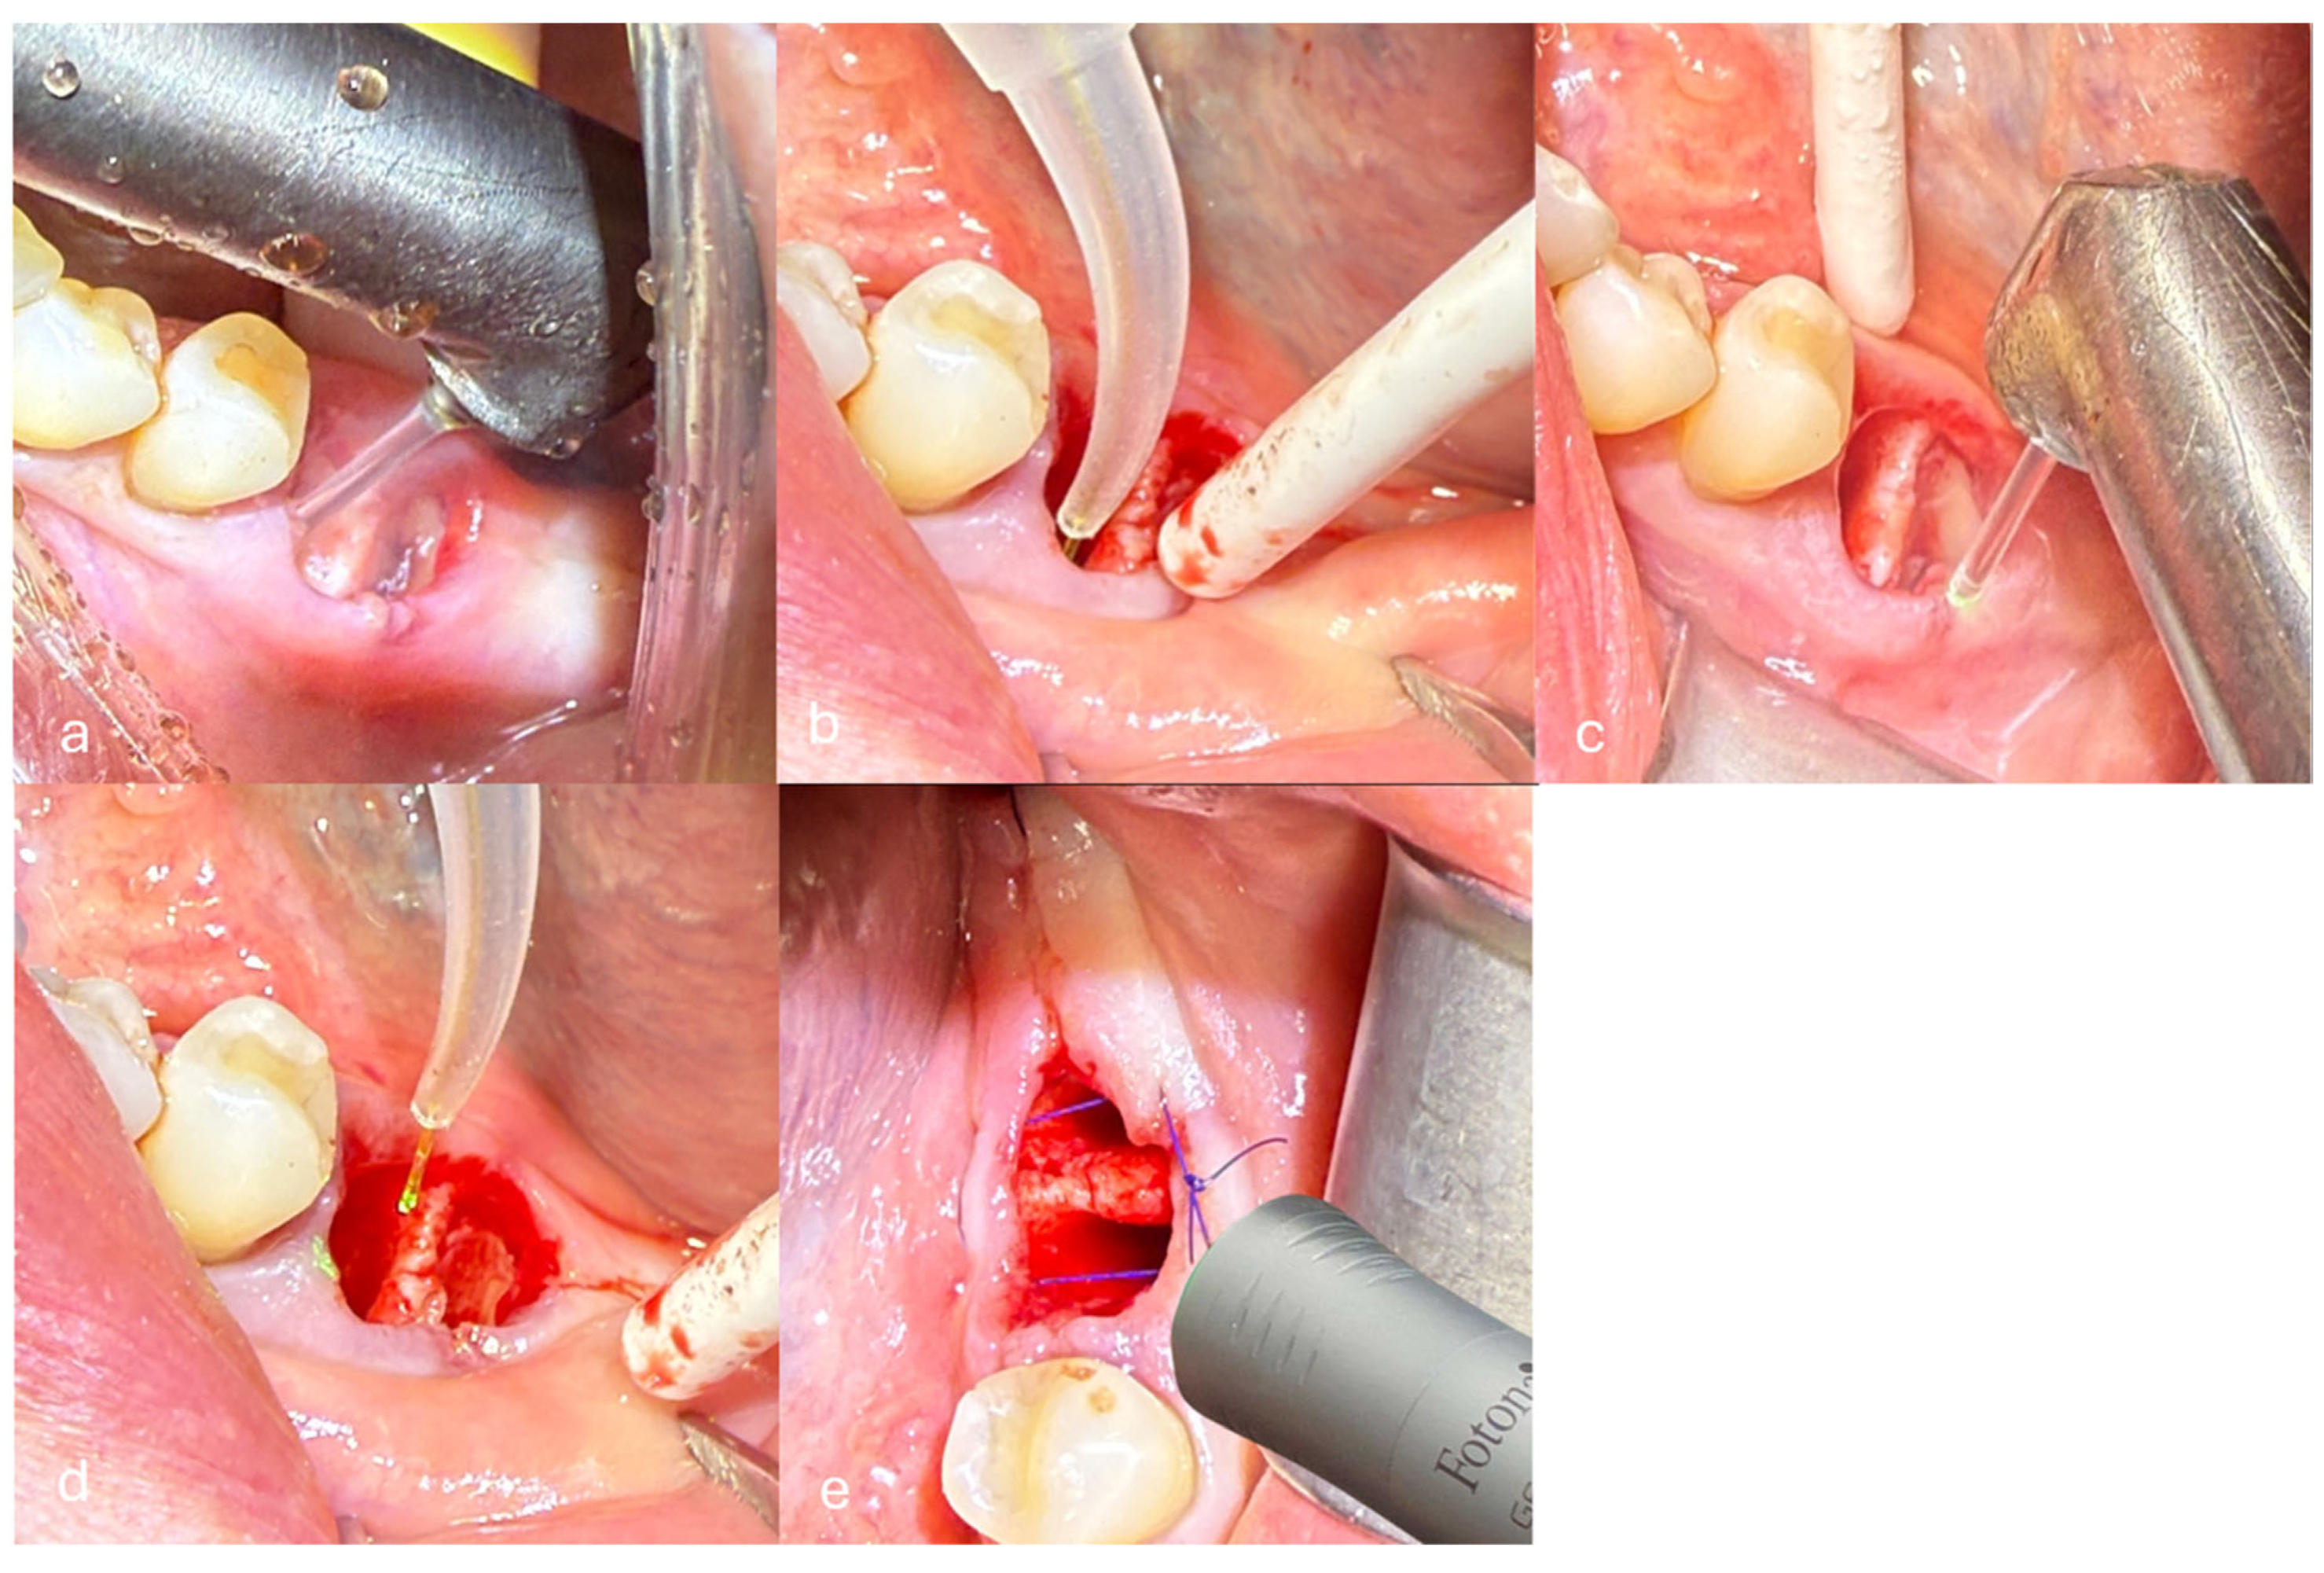

- Removal of inflamed granulation tissue and debridement of the alveolus were performed using the Er:YAG laser with the H14 handpiece and a cylindrical tip of 1.3 mm diameter in non-contact mode with a non-activated tip. The laser operated with a pulse duration of 300 µs (Short Pulse mode, SP), energy of 160 mJ, frequency of 15 Hz, and water/air settings of 4/2. The calculated fluence was approximately 12.05 J/cm2, and the power density was 184.61 W/cm2 (Figure 2a).

- Deep disinfection of the alveolus was performed using the Nd:YAG laser with a 300 μm fiber in non-contact and non-activated mode. The laser operated with a pulse duration of 300 µs (SP), power of 2 W, and frequency of 20 Hz. The calculated fluence was approximately 143 J/cm2, and the power density was 2829.42 W/cm2 (Figure 2b).

- De-epithelialization of the keratinized gingiva to the mucogingival junction was performed using the Er:YAG laser with the H14 handpiece and a cylindrical tip of 1.3 mm diameter in non-contact mode and a non-activated tip. The laser operated with a pulse duration of 300 µs (SP), energy of 120 mJ, frequency of 20 Hz, and water/air settings of 4/2. The calculated fluence was approximately 9.04 J/cm2, and the power density was 184.61 W/cm2 (Figure 2c).

- Stabilization of the blood clot was performed using the Nd:YAG laser with a 300 μm fiber in non-contact and non-activated mode. The laser operated with a pulse duration of 500 µs (Long Pulse mode, LP), power of 4 W, and frequency of 15 Hz. The calculated fluence was approximately 377 J/cm2, and the power density was 5658.84 W/cm2 (Figure 2d).

- Photobiomodulation (PBM) was performed using the Nd:YAG laser with the Genova flat-top handpiece (spot size 0.95 cm2) in Micro Short Pulse (MSP) mode. The laser operated with a power of 0.5 W and a frequency of 10 Hz. PBM was applied to the post-extraction socket in three points/locations: buccally (vestibular side), lingually, and occlusally (from the top of the socket). Each point was irradiated for 60 s per session. The delivered fluence per session was approximately 31.58 J/cm2, and the power density was 0.53 W/cm2. PBM was performed on days 0, 3, 5, and 7 post-extraction (Figure 2e).